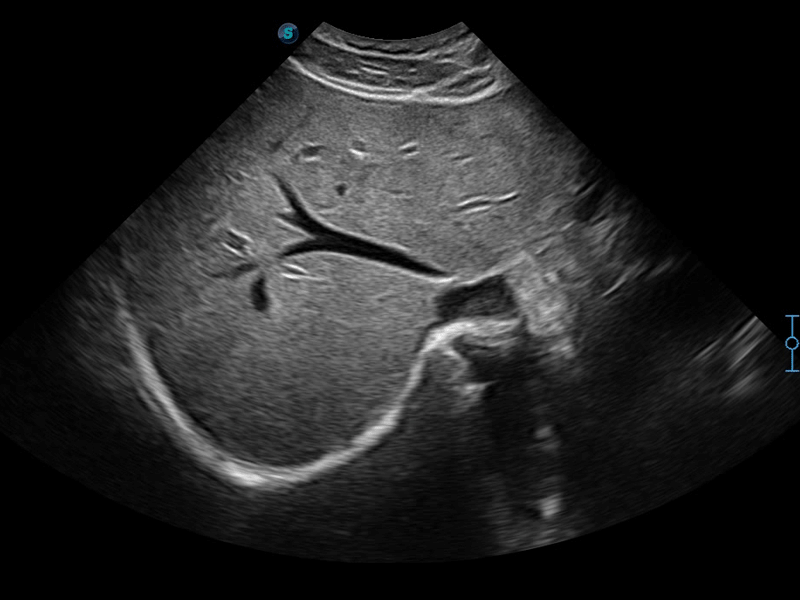

開立醫(yī)療通過不斷的技術(shù)創(chuàng)新,為大眾的生命健康提供持續(xù)關(guān)愛。P12 Plus采用全新一代超聲成像平臺(tái),新平臺(tái)旨在將真實(shí)還原組織解剖結(jié)構(gòu)作為首要目標(biāo)。平臺(tái)采用全新集成化硬件模塊,搭載新一代芯片,系統(tǒng)性能得到大幅提升,為您的診斷提供了豐富的臨床信息。優(yōu)異的圖像表現(xiàn),豐富的探頭配置,全面的應(yīng)用功能,為您日常診斷提供了可靠的助手。

彩色多普勒超聲診斷系統(tǒng)